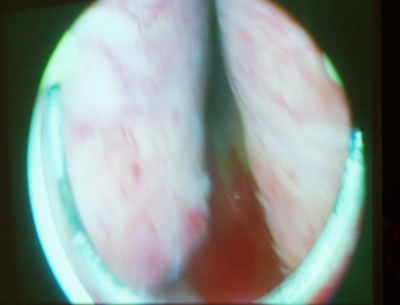

Ревизия простатического отдела уретры. Видны гиперплазированные

левая и правая доли предстательной железы, петля резектоскопа.